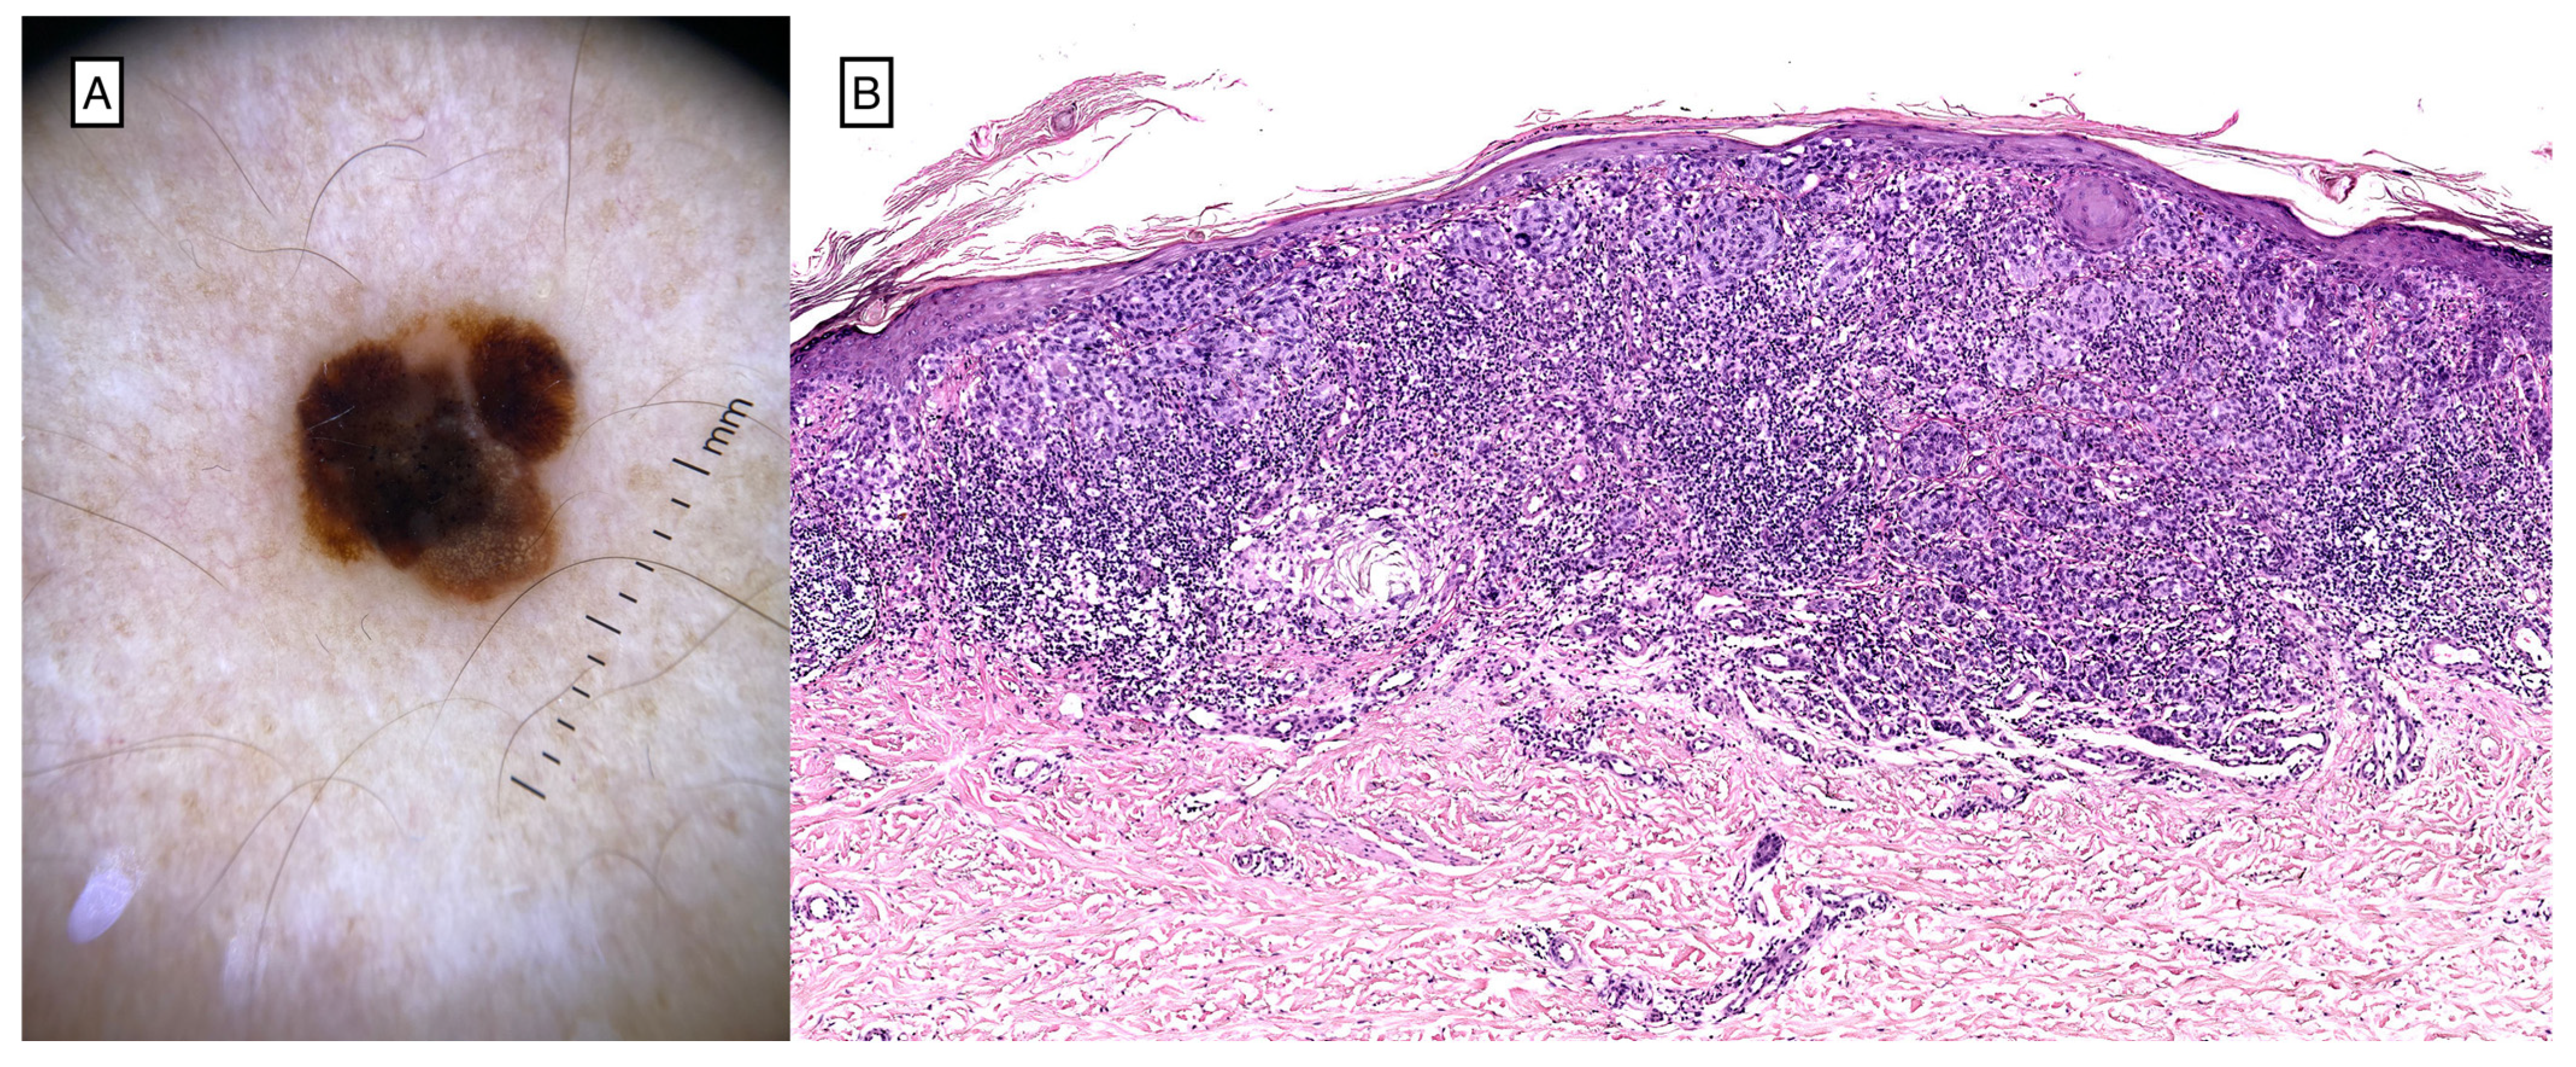

- Zimmer, L.; Hillen, U.; Livingstone, E.; Lacouture, M.E.; Busam, K.; Carvajal, R.D.; Egberts, F.; Hauschild, A.; Kashani-Sabet, M.; Goldinger, S.M.; et al. Atypical melanocytic proliferations and new primary melanomas in patients with advanced melanoma undergoing selective BRAF inhibition. J. Clin. Oncol. Off. J. Am. Soc. Clin. Oncol. 2012, 30, 2375–2383. [Google Scholar] [CrossRef]

- Dalle, S.; Poulalhon, N.; Debarbieux, S. Tracking of second primary melanomas in vemurafenib-treated patients. JAMA Dermatol. 2013, 149, 488–490. [Google Scholar] [CrossRef]